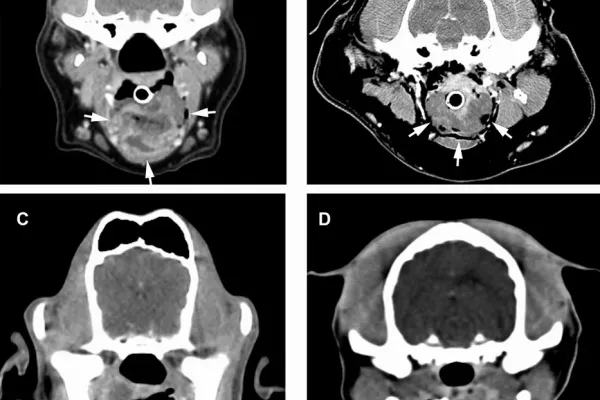

Hlava a krk:

Zobrazení a diagnostika patologií v dutině nosní (nádory, chronické záněty, cizí tělesa). Zlomeniny čelistí. Hluboké procesy v nosohltanu a krku (nasopharyngeální abscesy). Patologie v oblasti oka. Některé nádorové procesy mozku a lebky. Fraktury lebky, krvácení do mozku. Poranění krční páteře. Poranění dýchací trubice či hrtanu.